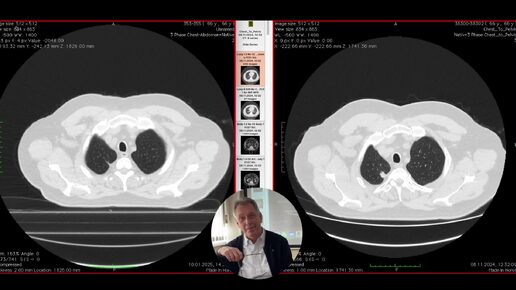

КТ реанимационного пациента.